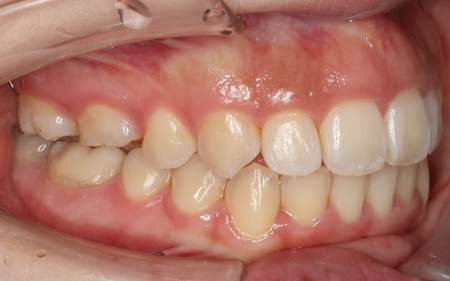

20代女性 ワイヤー矯正とマウスピース矯正を併用したハイブリッド矯正で歯並びを改善した症例

拝見したところ、上下の歯が正しく並ぶためのスペースが足りず、デコボコに生えていました。

とくに、犬歯が正しい歯並びから大きく飛び出した位置に生えており、いわゆる八重歯の状態です。

また、奥歯を噛み合わせた際に上下前歯が噛み合わず隙間ができる開咬(かいこう)も認められました。